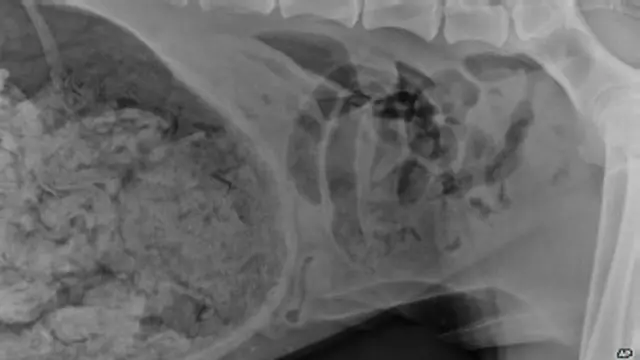

ABD'de hasta bir köpeği ameliyat eden veterinerlerin, hayvanın midesinden 43,5 adet çorap çıkardığı ortaya çıktı.

64 kiloluk Danua cinsi köpek çorap çiğnemeye düşkün olmasıyla tanınıyordu ama, kimse, köpeğin çorapları olduğu gibi yuttuğunun farkına varmamıştı.

Köpeği Şubat ayında ameliyat eden veterinerler o güne dek bir hayvanın midesinden hiç bu kadar çok sayıda çorap çıkarmamış olduklarını anlattılar.